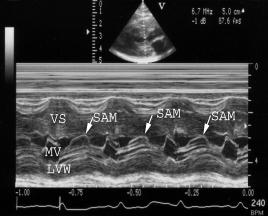

This image shows systolic anterior mitral valve motion (SAM) (arrows). The mitral valve is pulled up into the left ventricular outflow tract during systole. SAM can be created by a venturi effect as high flow velocity in a narrowed outflow tract drags the leaflet upwards. It may also be produced by abnormal alignment of the papillary muscles resulting in displacement of the mitral leaflet during systole. Regardless of the cause, its presence implies outflow obstruction. Below are more examples of SAM on m-mode and 2D images. |

Arrows show the systolic anterior mitral valve motion (SAM). Use the left ventricular wall motion to help you identify the systolic time period. VS = ventricular septum, MV = mitral valve, LVW = left ventricular wall, RV = right ventricle, LV = left ventricle, AO = aorta, LA = left atrium, MVd = mitral valve in diastole |